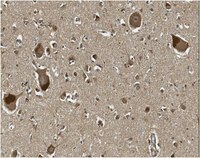

This Anti-Oligodendrocyte transcription factor 2 (OLIG2 antibody is validated for use in WB, IH(P) for the detection of Oligodendrocyte transcription factor 2 (OLIG2.

More>> This Anti-Oligodendrocyte transcription factor 2 (OLIG2 antibody is validated for use in WB, IH(P) for the detection of Oligodendrocyte transcription factor 2 (OLIG2. Less<<Recommended Products

| M, H | WB, IH(P) | Gp | Serum | Polyclonal Antibody |